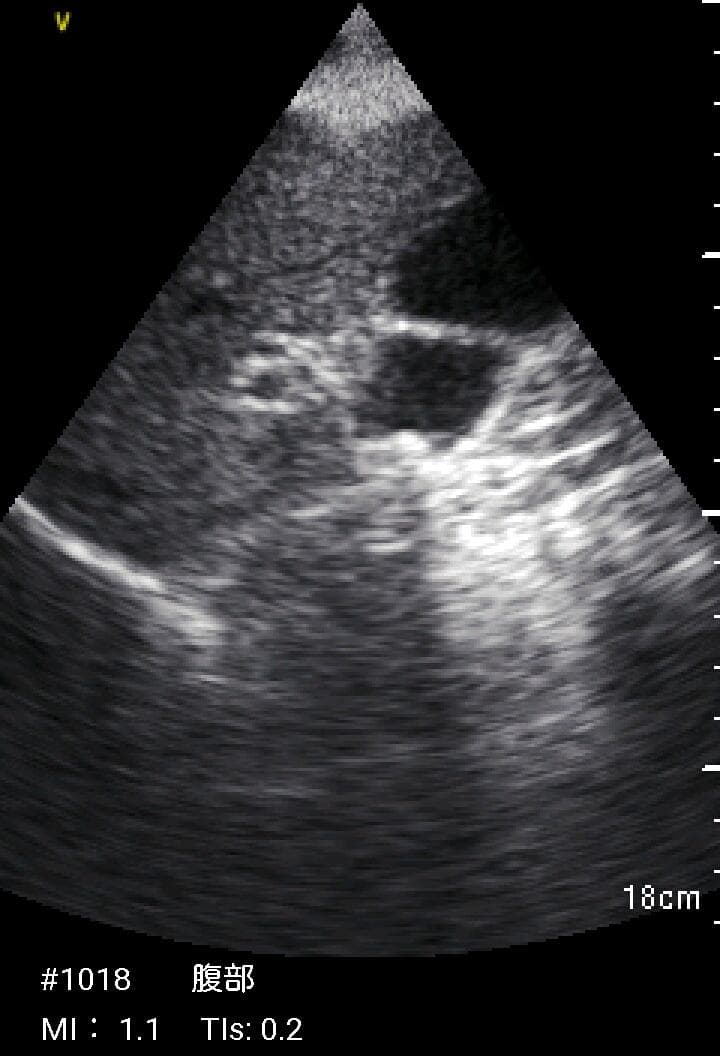

おわかりになる方のみの購入をお願いいたします実際に実施した写真をあげました正常肝臓、胆石症、頸動脈プラーク、同じく頸動脈プラーク、Mrの収縮期、同じくM弁の開放期とA弁の開放期、腹部大動脈瘤、正常の頸動脈、甲状腺右葉の結節、前立腺肥大画像の描出は条件によりますがご検討をお願いいたします経年変化、使用に伴うスレや傷などがあります機能に問題はありませんスキャンは心血管、腹部、体表に対応します外部接続端子のカバーが一部壊れていますが蓋は閉まりますバッテリーはフル充電されますが劣化はあると思います医療用モニタリング機器 Vscan Extend、GE- モデル名: Vscan Extend- ブランド: GE- 色: ホワイト- 機能: 医療用モニタリング機器ご覧いただきありがとうございます。セブンプレミアム 耳が痛くなりにくい やわらかマスク385枚。